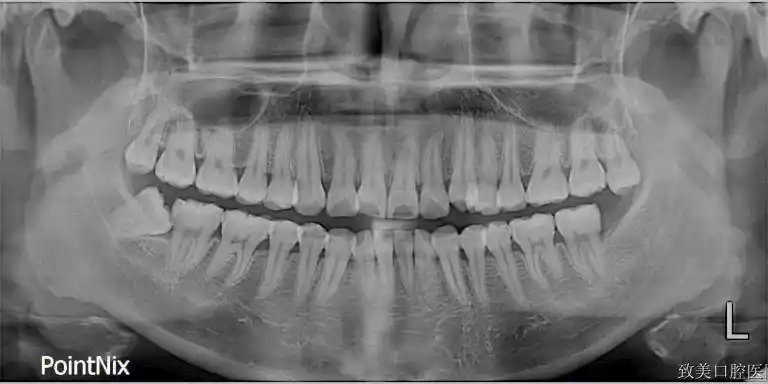

牙槽骨窄可以种植牙吗?种植牙对牙槽骨宽度有什么要求?

种牙牙槽骨的标准条件牙槽骨厚度3mm5mm7mm可以种牙吗